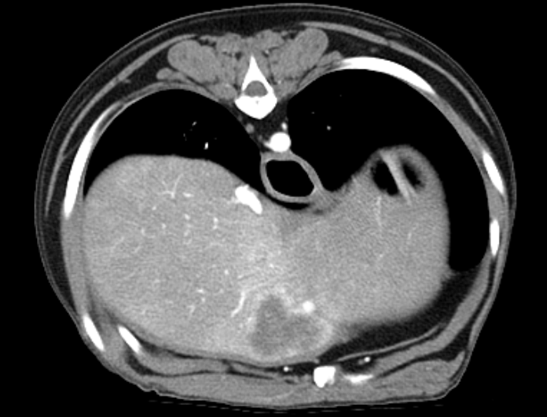

160ch CT

160 slice CT는 빠른 속도로 환자의 마취 시간을 줄이며(5분 이내) 정확한 진단에 도움을 줍니다. 또한 심장 등의 장기를 평가함에 있어 기존 64채널 CT에 비해

우수한 해상도의 영상을 획득 가능합니다.

160 slice CT는 국내 동물병원에서 최상급 촬영장비(Toshiba Acquilion Prime)에 해당하며 conventional CT 촬영 이외에도 추가적인 body perfusion,

dual energy 등도 가능합니다.

160채널 CT는 고화질 영상으로 숨어있는 비정상적인 문제점들을 찾아내어 진단 및 치료에 도움을 주고 있습니다.

Early arterial phase

Late arterial phase

Portal phase

Delayed phase

3D 재구성을 통해 외과의에게 더욱 정확한 정보를 제공할 수 있어 수술의 위험성을 감소시킵니다.

03복부 CT

· 간, 비장의 종양을 포함한 실질 변화 및 혈관기형(PSS)의 평가

· 소화기, 비뇨기 실질장기의 평가(종양, 이물, 염증 등)